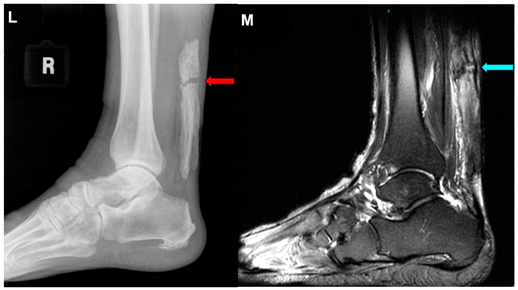

| Sullivan and Thurston, 2021 e [35] | A 72-year-old man. This image submission includes an ultrasound (Image K), lateral view x-ray (Image L), and an MRI (Image M) of a patient who presented to an orthopedic sports medicine clinic after feeling a “pop” while mowing his lawn. Image K is an ultrasound of the Achilles Tendon that depicts a segment of discontinuity (green arrow) within a linear hyperechoic signal. Image L and Image M show ossification of the Achilles Tendon and arrows (red and blue, respectively) indicate fracture of the ossified mass. The patient had no knowledge of the ossification, but he reported having lower leg surgery as a 2-year-old to correct for in-toeing. The patient was treated conservatively with casting and physical therapy. One year after the ossification and coexisting fracture of the ossified mass was discovered, he reported being fully functional without pain. | ![]() ![]() |